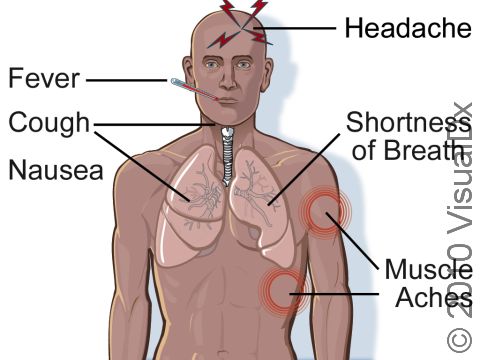

Signs & Symptoms

Avian influenza causes a flu-like illness.

Mild symptoms include:

- Fever

- Cough

- Feeling generally weak and achy (malaise)

Sore throat

More severe symptoms include:

- Pneumonia

- Respiratory failure

- Death